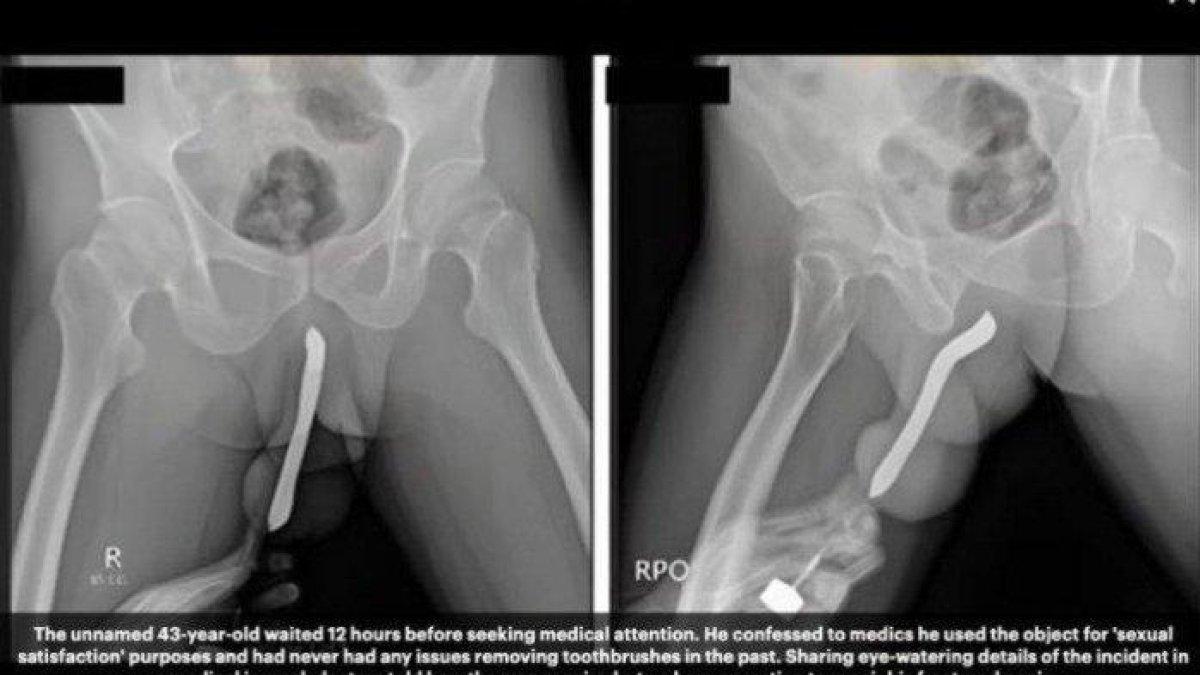

"Dia memiliki riwayat memasukkan sikat gigi ke bagian punggung dan perut penisnya melalui sayatan kecil di rumahnya pada tahun 2017 untuk kepuasan seksual.

Oleh karena itu, pasien telah menyimpan alat tersebut di penisnya selama enam tahun," tulis laporan jurnal tersebut.

Akibat cedera tersebut, pasien harus menjalani operasi yang dilakukan oleh seorang ahli urologi dengan spesialisasi trauma dan rekonstruksi.

Dokter yang menangani pasien mengatakan, salah satu kesulitan operasi pada kasus ini adalah ketika melepaskan sikat gigi yang terlanjur menempel pada jaringan di sekitarnya.

Operasi dilakukan selama dua jam dengan total volume kehilangan darah kurang lebih sebanyak 100–150 mililiter.

Pasien kemudian dipulangkan tiga hari setelah operasi dan dilaporkan tidak ada komplikasi saat pemulihan pasca operasi.

Satu bulan setelah operasi, pasien melaporkan tidak adanya kelainan bentuk dan fungsi seksual serta kelainan buang air kecil.